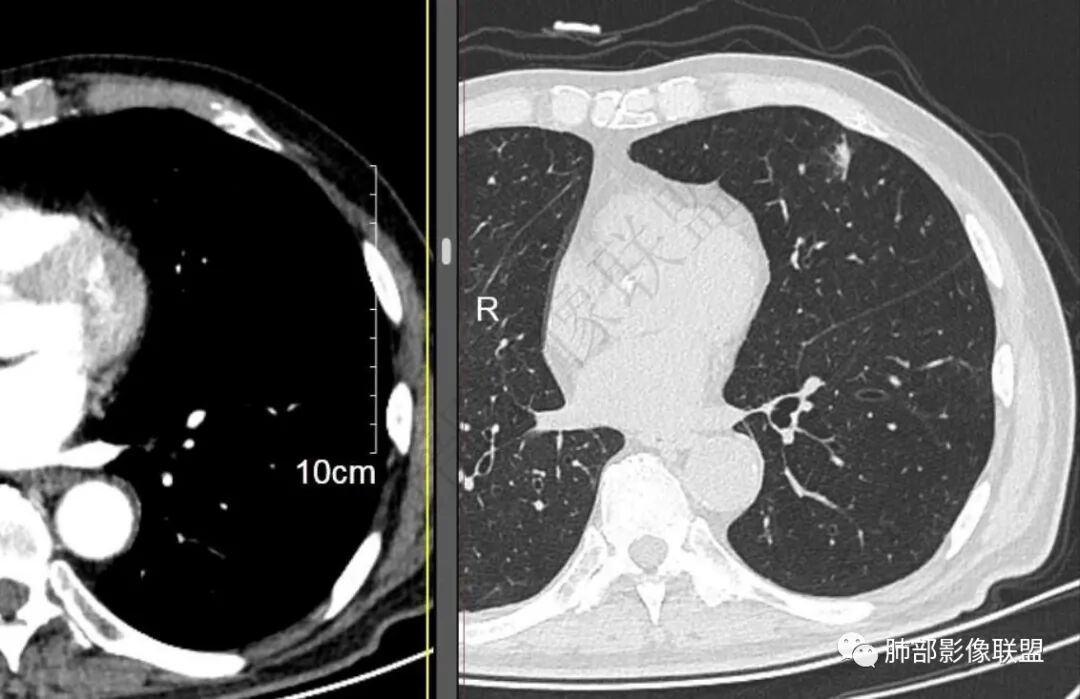

再1个多月后病灶继续增大,较明显不均匀强化,肺门一侧见低密度区。病灶边缘相对不清,可见毛刺。

三.病程脉络相当清楚,即病灶进行性增大,易想到新生物或转移瘤,但经验上分析增长速度显然太快,尤其是对于原发肺腺癌或者肺鳞癌而言,单发转移瘤也较少这样的进展速度。

四.单就影像而言,病灶肿瘤特征不够充分,恶性肿瘤病史,隐球菌等特殊感染确实不能排除。

五.尽管本例鳞癌的病例意见出乎预料,但部分低分化肿瘤迅速增长也不时出现,仍须警惕!